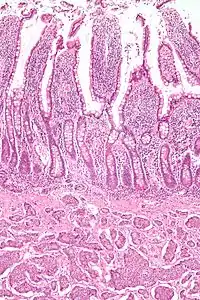

| Micrograph of a neuroendocrine tumor. H&E stain | |